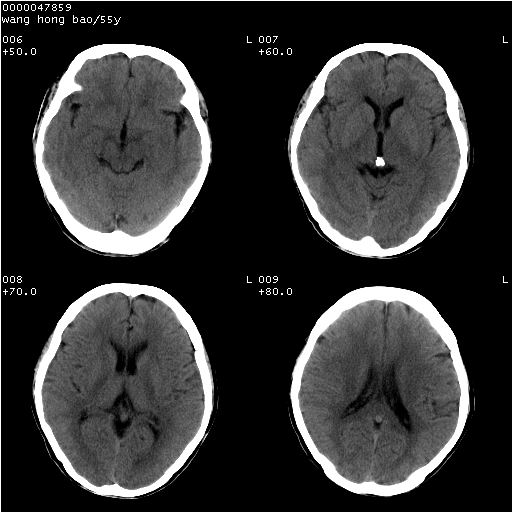

以下是引用dyqct在2008-5-3 23:36:00的发言:[br]桥前池区可疑蛛网膜囊肿。其它未见明显异常。建议做mri。

以下是引用qiushi在2008-5-4 10:10:00的发言:[br]鞍上池前缘突出影为双侧额叶直回;箭头所指为双侧正常之人字缝.[br]桥前池区可疑表皮样囊肿或蛛网膜囊肿,必要时mri

以下是引用zjzjr在2008-5-4 14:50:00的发言:[br]桥前池区可疑蛛网膜囊肿。其它未见明显异常。建议做mri。